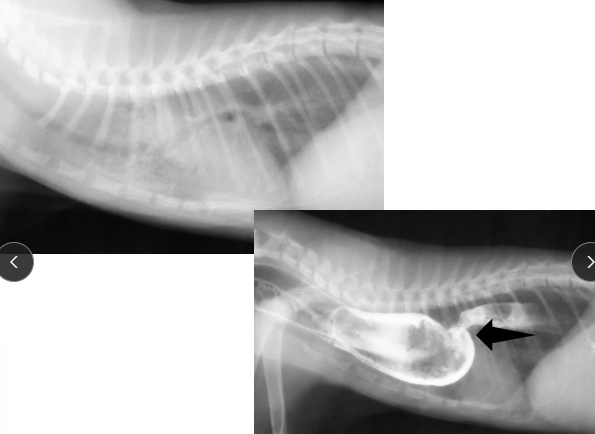

Megaesophagus

Et: Congenital, Idiopathic (#1 dogs), MG, Hiatal hernia, Reflux esophagitis

R/O: Esophageal Obstruction → cause diffusely dilated esophagus

Sig:

Congenital: kittens + GSD/Shar Pei puppies

Acquired: GSD, Golden

Cs: Regurg after weaning, Diffuse dilation, weight loss

Cats: Uncommon, Hiatal hernia and reflux esophagitis underlaying causes

Dt: lab work, Rads, barium esophagram, AchR antibody (MG 25%)**, cortisol, lead, thyroid

Tx: upright feeding (Bailey chair), small soft meals, G tube feeding, pyridostigmine (MG), immunosuppressives (MG)

Avoid promotility agents

Px: May improve but not normal

better w/ MG, recurrent pneumonia